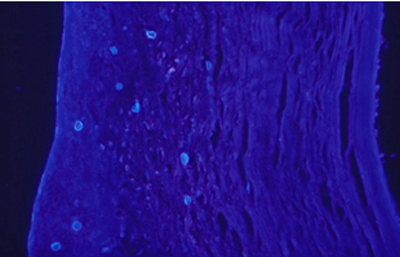

Cuando el examen patológico se realiza en cortes de tejido corneal procesados en parafina, (biopsias y discos de córnea de queratoplastias) las coloraciones que empleamos usualmente son la coloración de Hematoxilina-Eosina (Figura 49), el Blanco de Calcofluor. (Figura 50), la de PAS (Figura 51 y 52). De nuevo, la consideración de que una infección corneal puede ser causada por Acantamoebas es la condición indispensable en el diagnóstico diferencial para llegar a su diagnóstico

Fig. 49 H-E, Original x160

Fig. 50 CW, Original x160

Fig. 51 PAS, Original x160

Fig. 52 PAS, Original x160